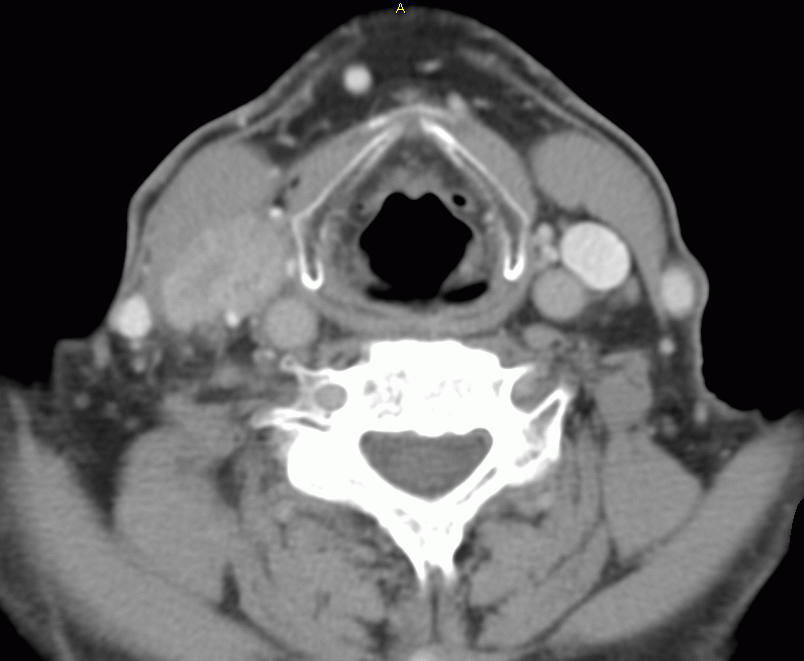

64-jähriger Mann mit stenosierendem supraglottischem T3-Tumor mit LK-Metastasen rechts.-![]() |